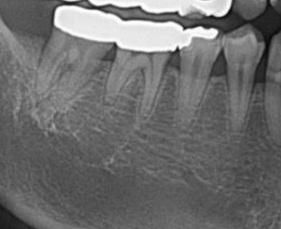

어금니 치료방법 알수잇을까요.,,?

치료방법이알고싶습니다. 염증소견잇다고들엇고

흔들리기는하지만 아프지도 식사하는데문제가없습니다

Ct입니다

치아가 흔들리는 정도라면 잇몸치료를 바로 시작하시는 것이 좋겠고 발치도 염두해둬야 합니다.

일단은 전체적으로 스켈링을 하고나서 잇몸치료를 받아보시고 계속해서 불편하면 신경치료를 하셔야될것같습니다.

사진으로 봤을 경우에는 크게 문제가 있어 보이진 않습니다. 하지만 해당치에 불편감이 있으면 뿌리에 금이 갔거나 했을 가능성이 높습니다.

단순히 치아가 과도하게 물려서 생기는 불편감이라면 높이를 조정하면 괜찮아집니다. 하지만 치아뿌리의 금이 같거나 했다면 치아를 발치해야 하는 경우도 생길 수 있습니다.

염증잡기 위해서 신경치료를 해볼순 있습니다 다만 신경치료가 원래 무조건 성공하는 걸지는 장담할 수 없습니다